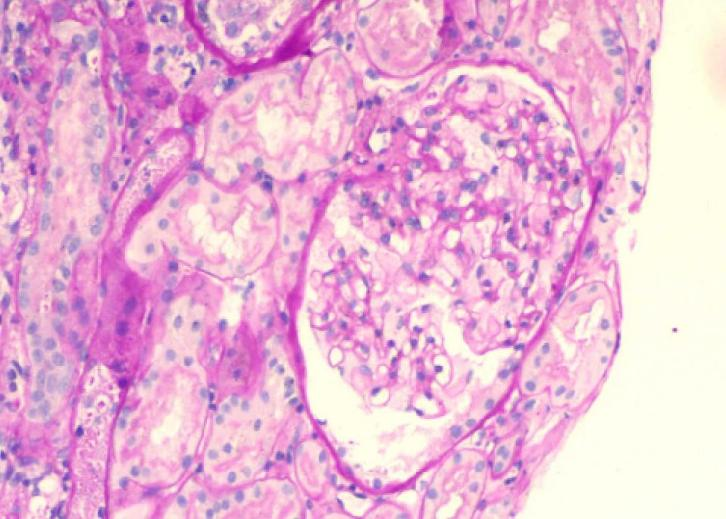

光镜形态表现

光镜标本下包括肾皮质及髓质,可见20个肾小球,其中5个肾小球球性硬化,5个肾小球节段性硬化;

节段性硬化区域周边足细胞增生、肥大,另见个别肾小球球囊周纤维化,其内毛细血管袢缺血皱缩;

其余肾小球足细胞明显肿胀,空泡变性呈泡沫状,系膜细胞和基质轻微增生,系膜区可见少量嗜复红蛋白沉积;

毛细血管襻开放,基底膜无明显增厚,未见钉突样结构,无系膜插入及双轨形成,上皮下、内皮下无明显嗜复红蛋白沉积,壁层上皮细胞无明显增生,未见新月体形成;

PAS×200 肾小球上皮细胞肿胀伴空泡变性、泡沫细胞形成